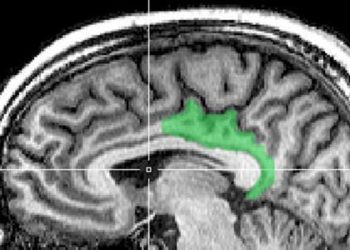

1. Among cognitively-intact elderly adults, magnetic resonance (MR) imaging using an arterial spin labeling (ASL) technique was shown to predict ...